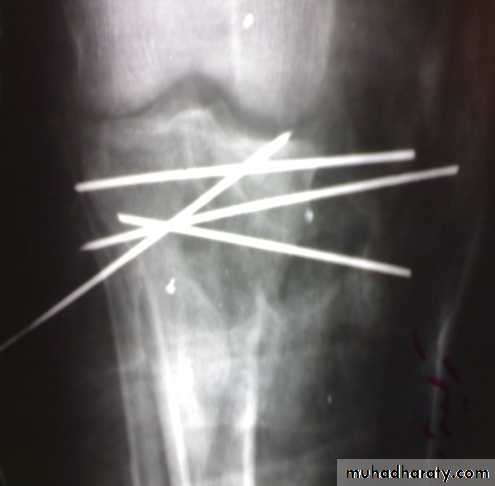

Tibial plateau fractures

Treatment

Aspirate hemarthrosis.Minimally displaced fractures: compression bandage, gradual exercise,then functional brace and gradual exercise after 3 wks.

Displaced and/ or comminuted lateral or medial tibial condyle fracture

Treatment:ORIF.

Associated ligament injury repaired.

Bicondylar fracture: needs ORIF with plate and screws or external fixation.